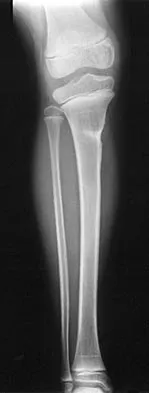

A 45-year-old male karate instructor sustained the injury shown in Figures 40a through 40c while practicing karate. The decision to proceed with surgery depends on which of the following factors?

Explanation

The most important criteria in determining the need for surgery following a nondisplaced or minimally displaced tibial plateau fracture is knee stability to varus/valgus stress. Soft-tissue injury noted on MRI may be addressed at a later time following fracture healing. This fracture pattern is amenable to nonsurgical management. Decisions regarding surgical intervention may be made up to 2 weeks after injury.